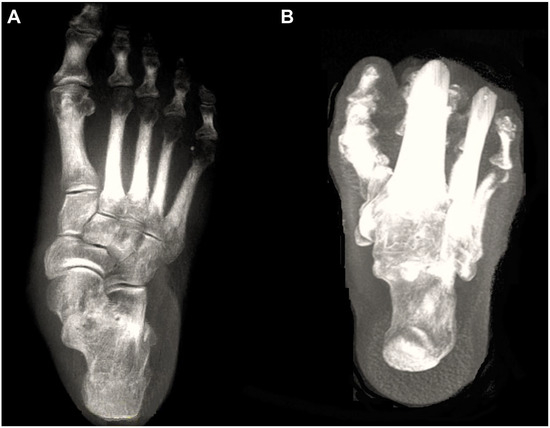

Figure 1.

Digitally reconstructed radiographs (DRRs) demonstrating foot anteroposterior (A) and hindfoot alignment (B) views.